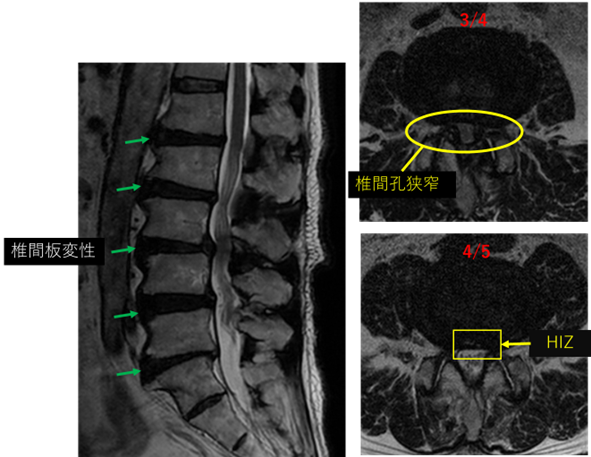

画像及び所見について

L1/2: 変性

L2/3: 変性、膨隆

L3/4: 変性、膨隆、脊柱管狭窄、左椎間孔狭窄、終板変性

L4/5: 変性、膨隆、線維輪断裂、左椎間孔狭窄

L5/S: 変性、膨隆、減高

以上の事が画像上認められます。

L3/4、4/5、5/S に

脊柱管狭窄、椎間孔狭窄、線維輪断裂、椎間板変性、終板変性 を認め、主症状の原因の可能性が高い。